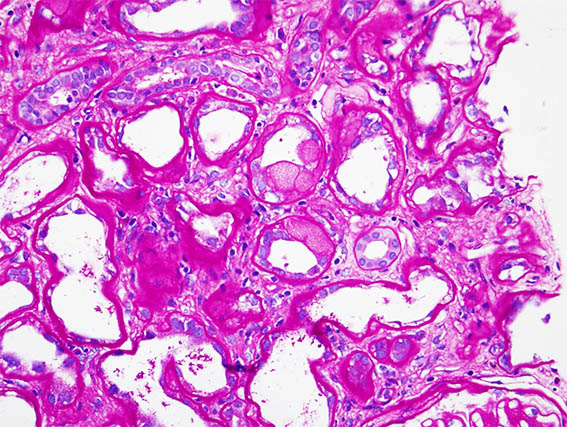

Una paciente de 41 años con diabetes mellitus de larga evolución desarrolló síndrome nefrótico abrupto, por lo que se le realizó una biopsia renal. La biopsia muestra nefropatía diabética avanzada sin GN superpuesta.

En una zona se identificaron lesiones tubulares como las que se ven en las siguientes imágenes:

Figura 3.

PAS, X400.